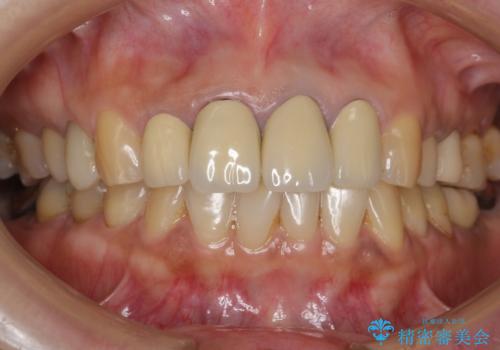

- 前歯のセラミック治療から5年経過した患者様です。

数年ぶりにメンテナンスに来て下さいました。

治療した上の前歯4本は全く問題がないそうで、「どうしてこんなに長持ちするんですか?」と聞かれた程です。

5年前のクラウン装着時と比較したところ、歯肉が成熟し歯間乳頭ができており、より天然歯のように自然に見えました。